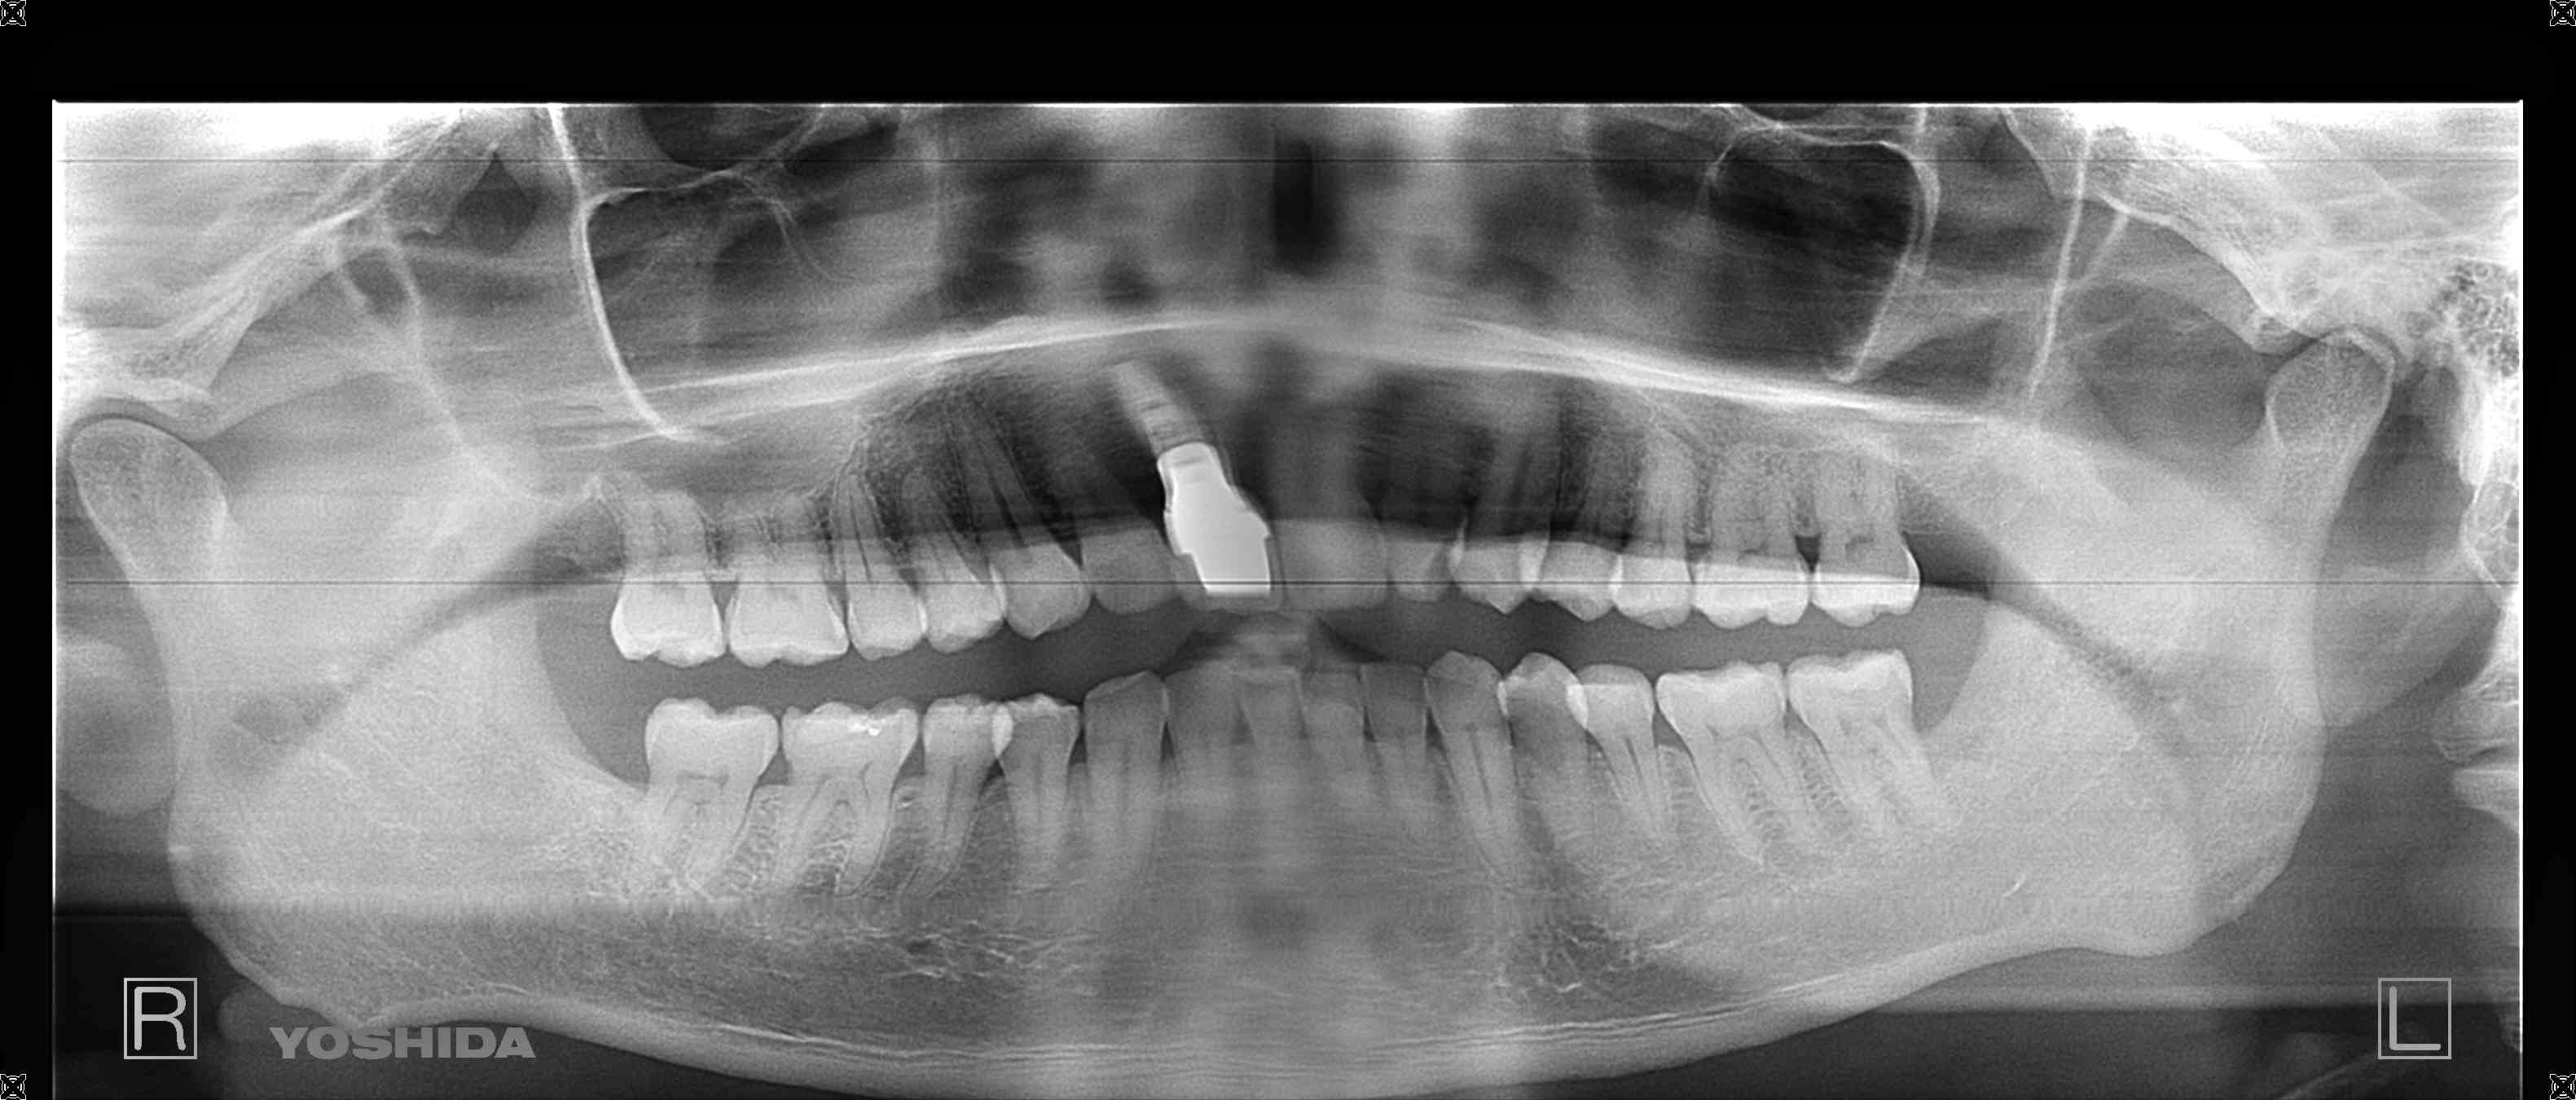

【レントゲン写真】

※下記写真はインプラントの被せ物が入った術後のレントゲン写真

抜歯後は骨の幅が不足していたため、骨造成(GBR)を併用し、約半年後にインプラント治療を行いました。